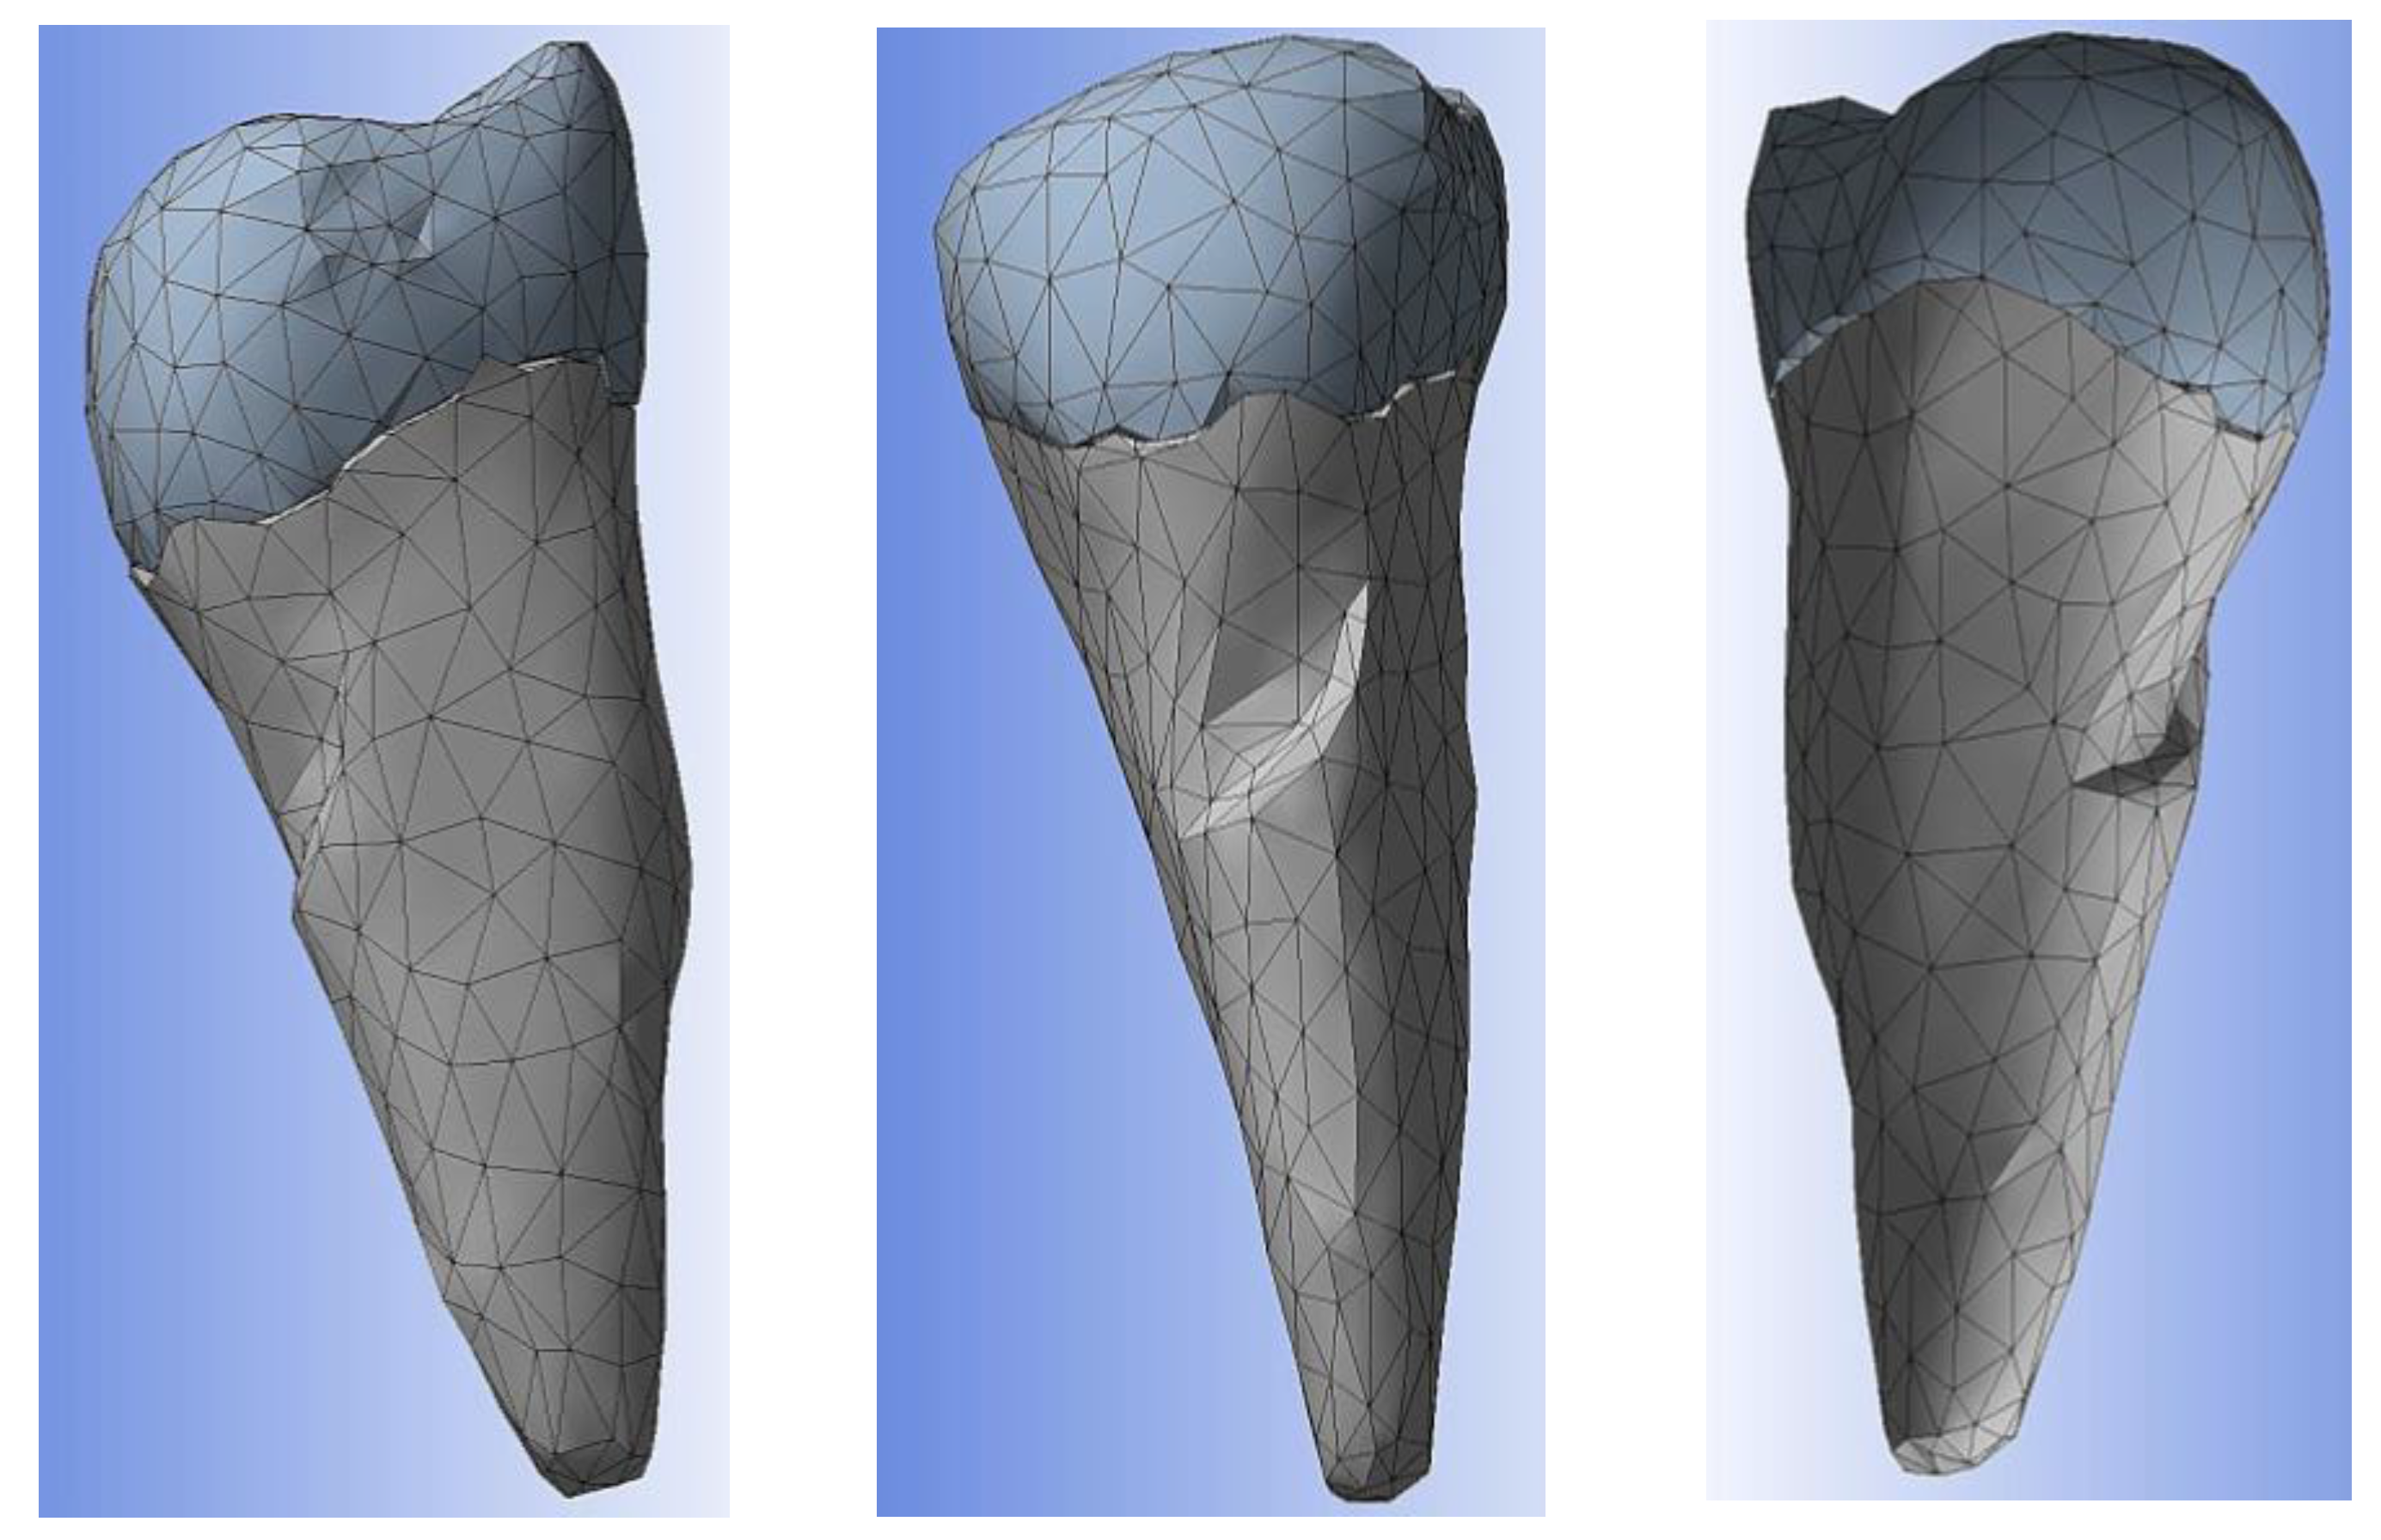

3. Finite Element Analysis (FEA) of Mandibular Right Premolars